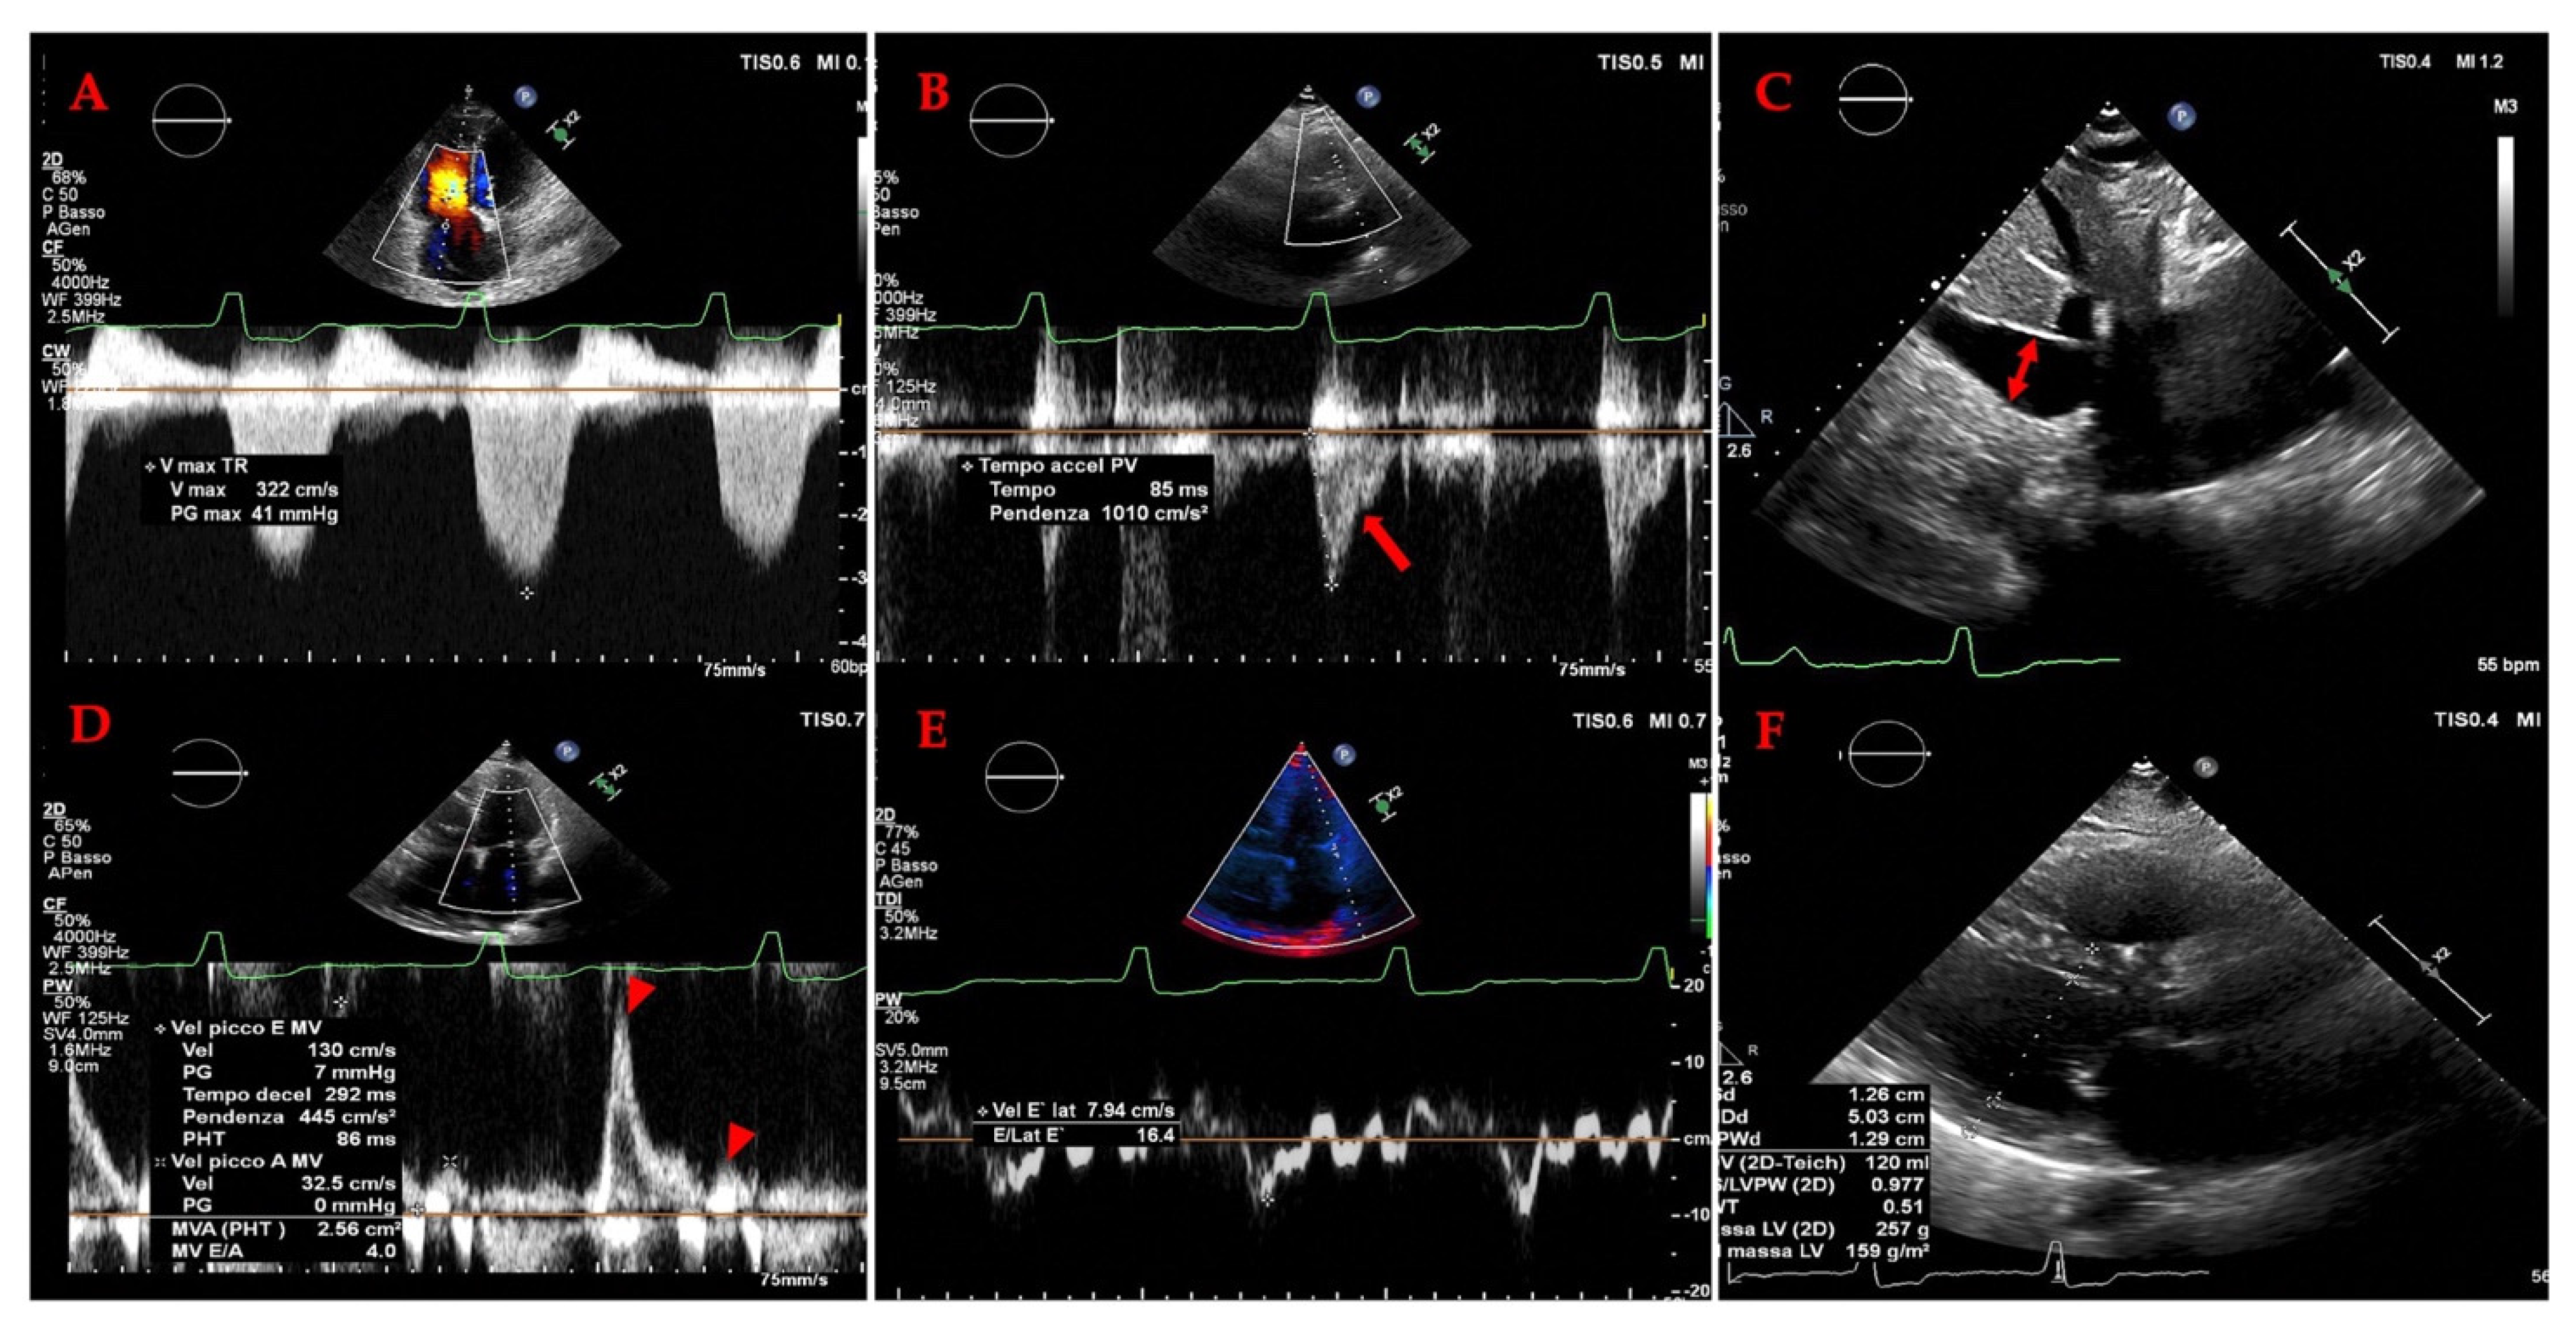

3.2. Cardiac Evaluation: Echocardiography

3.2.1. The Evolving Role of Echocardiography of Left Heart in Heart Failure

3.2.2. The Evolving Role of Echocardiography in Heart Failure: A Focus on the Right Heart and Pulmonary Hypertension (PH)